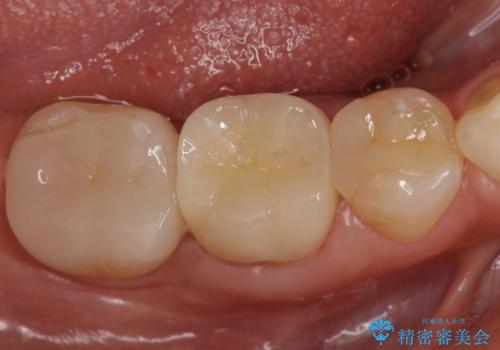

オールセラミッククラウン 急に痛み出した奥歯の治療